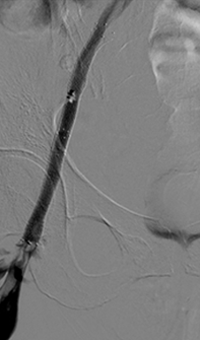

xray of occlusive thrombus extending into the iliac vein.

Occlusive thrombus extending into the iliac vein